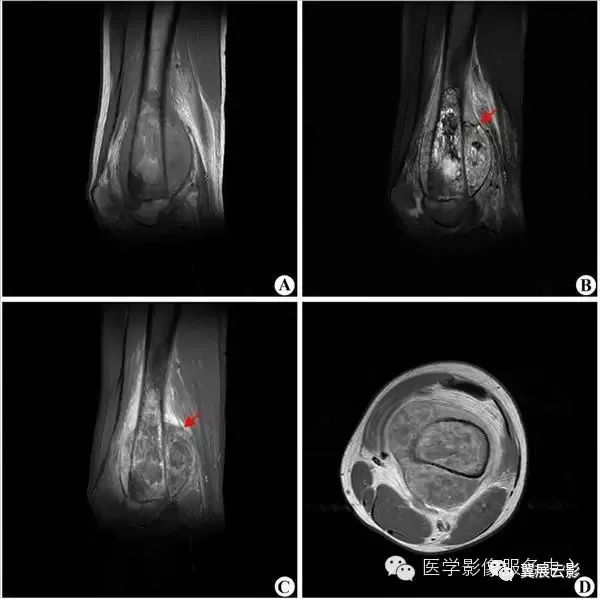

【MRI图片】:

【影像表现】:胫骨上段占位。T2WI(B、C)显示胫骨上段不均匀高信号肿块,膨胀明显;T1WI(A)肿块为低信号;增强扫描(D)肿块明显不均匀强化,中间有斑点状无强化区。【影像诊断】:胫骨上段骨巨细胞瘤。